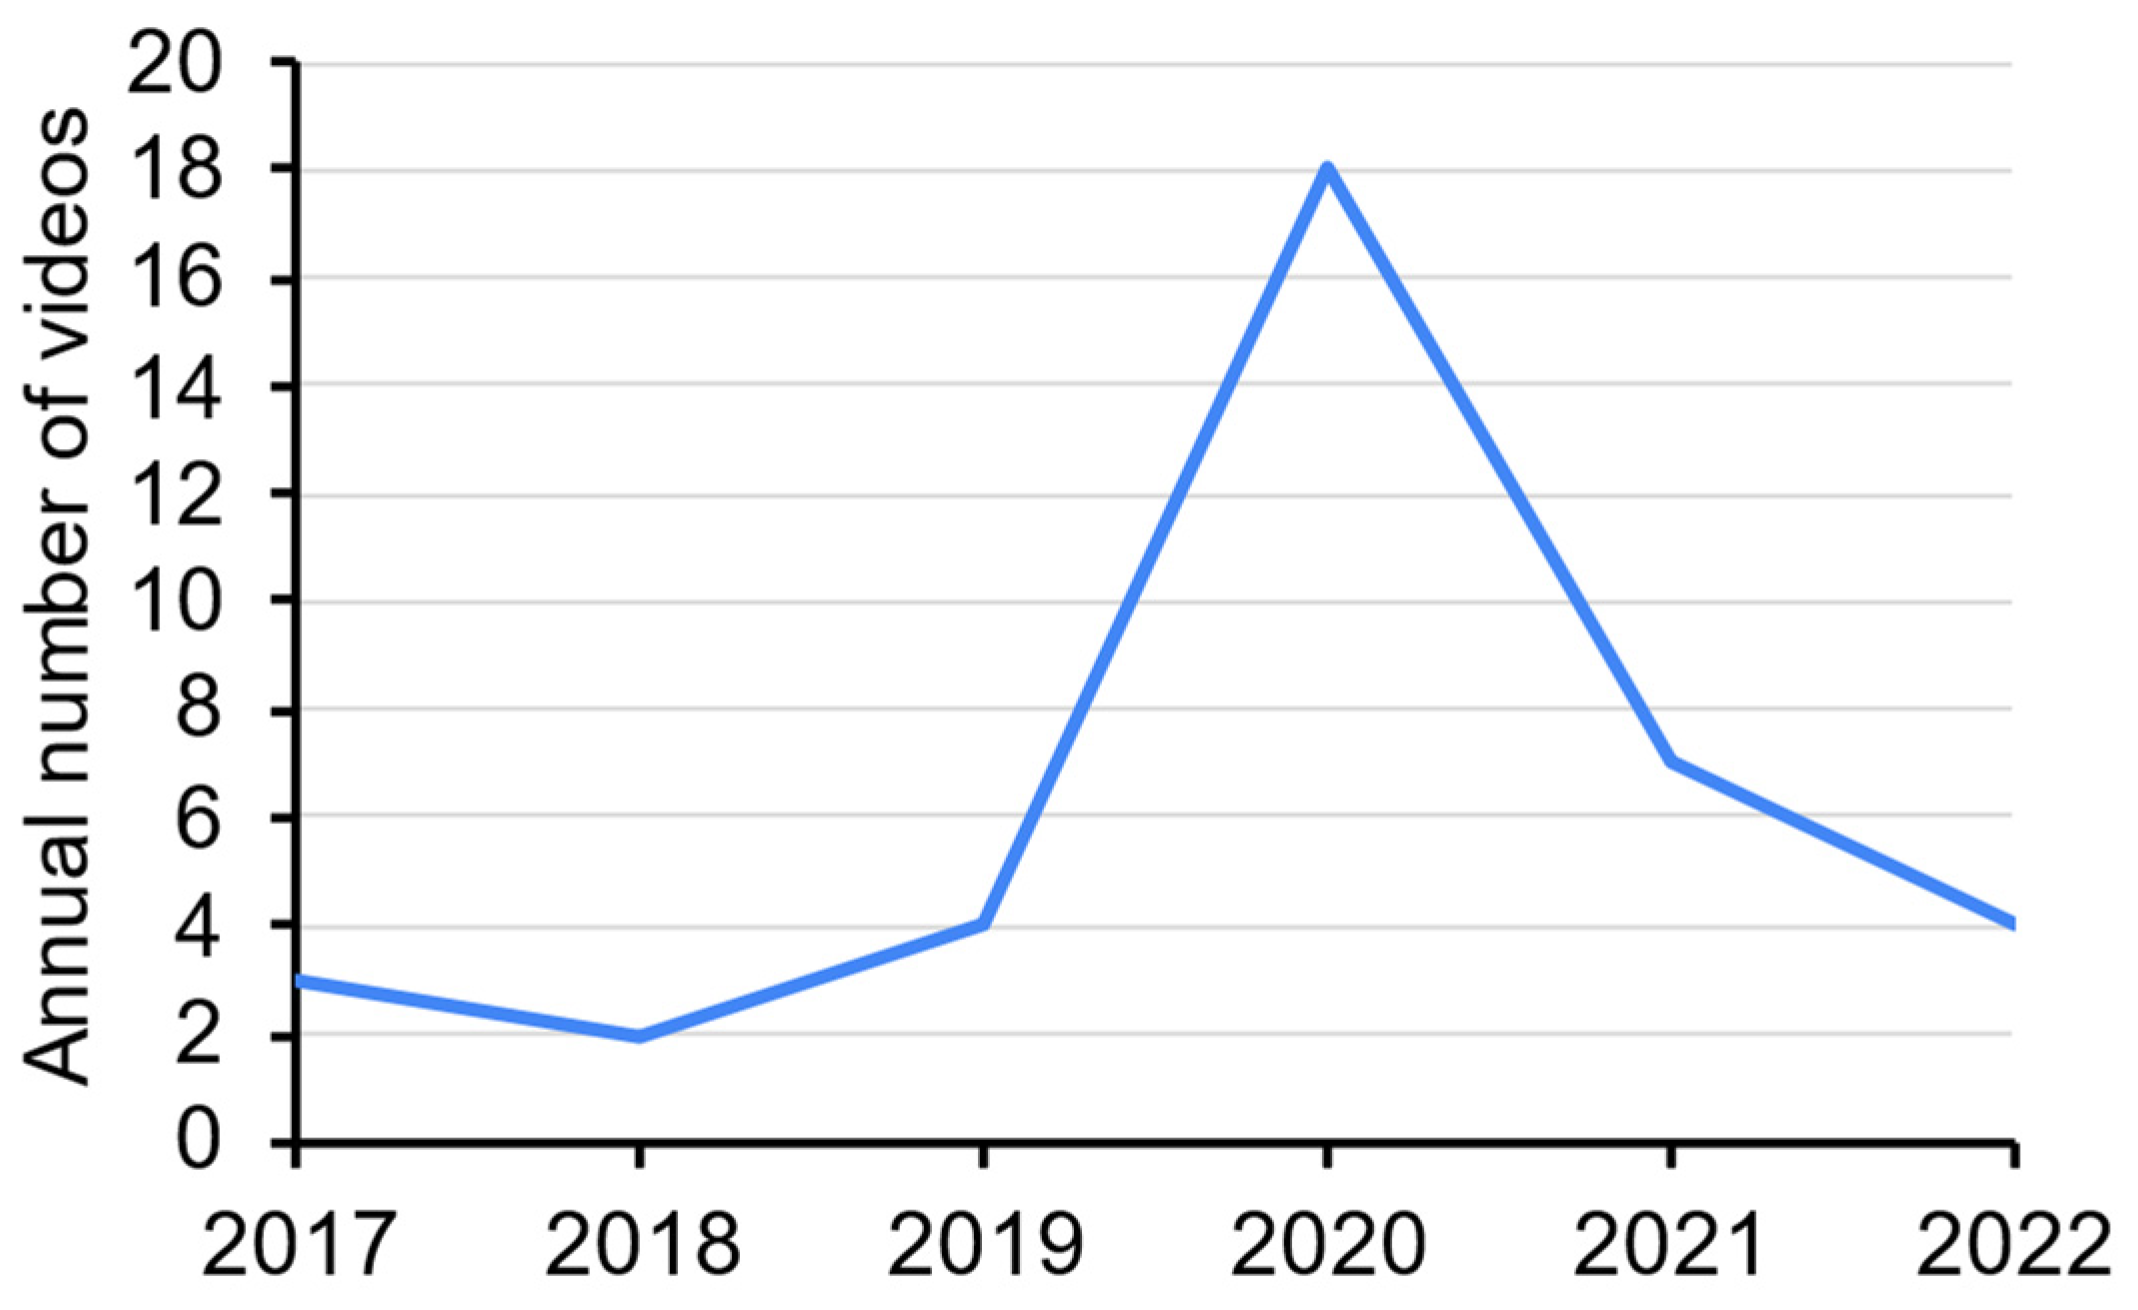

3. Results